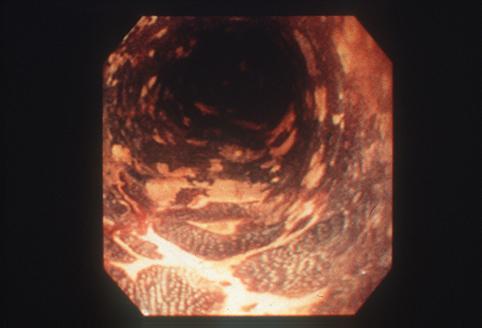

Criteria of Hist.ClassificationMalignant epithelial tumor/Squamous cell carcinoma

LocationEsophagus/Middle third

Technique, MethodEndoscopy

Macroscopic TypesType 0/IIc (IIc) Superficial depressed type

Size1 - 9

Depth of Tumor Invasionmucosa